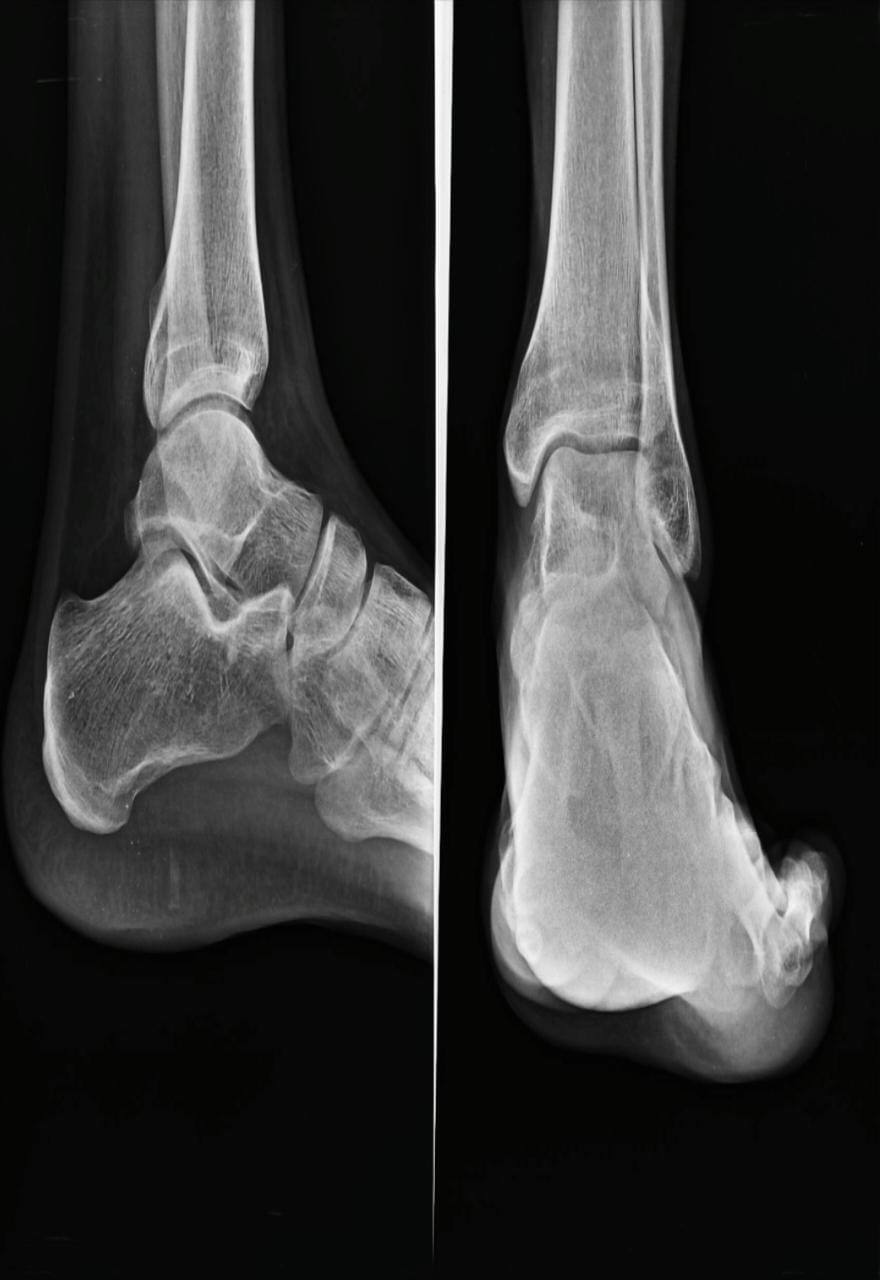

sir mera pair tree month pehale akel se mud gaya tha aur tisara x ray bhej rha hu kuch injury ho to bataye